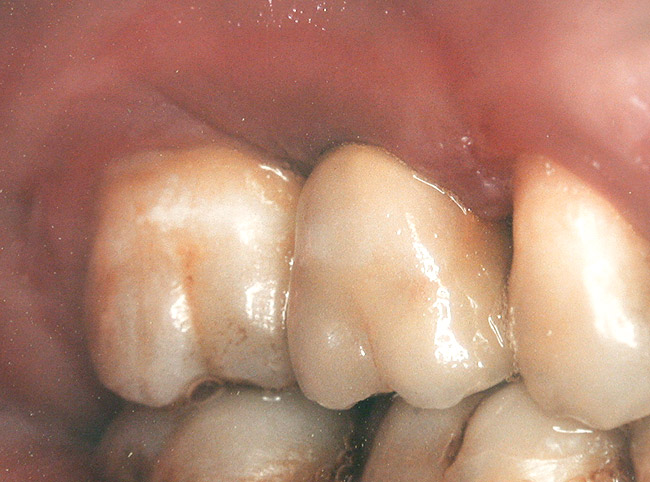

Case 3

A 53-year-old female was referred for evaluation of a fracture of tooth No. 24. The tooth had been treated endodontically 5 years prior. The radiograph revealed a complete fracture of the tooth involving the crown (Figure 12). Tooth extraction and immediate placement of a an implant that was 10 mm in length and 3.75 in diameter was planned.

At the time of surgery, the tooth was extracted without harvesting any mucosal flap because the implant site was prepared by means of a pilot drill bur (Figure 13) and alternating osteotomes (Figure 14A and Figure 14B). The implant was positioned and showed primary stability. The implant was loaded 2 days after surgery. Then, splinted PFM crowns supported by custom gold abutments were delivered. At 6 months posttreatment, the radiograph revealed no bone resorption and the clinical result was optimal (Figure 15A and Figure 15B).

Figure 15 A Final implant-supported PFM restorations.

Figure 15a  Final implant-supported PFM restorations.

Figure 15a